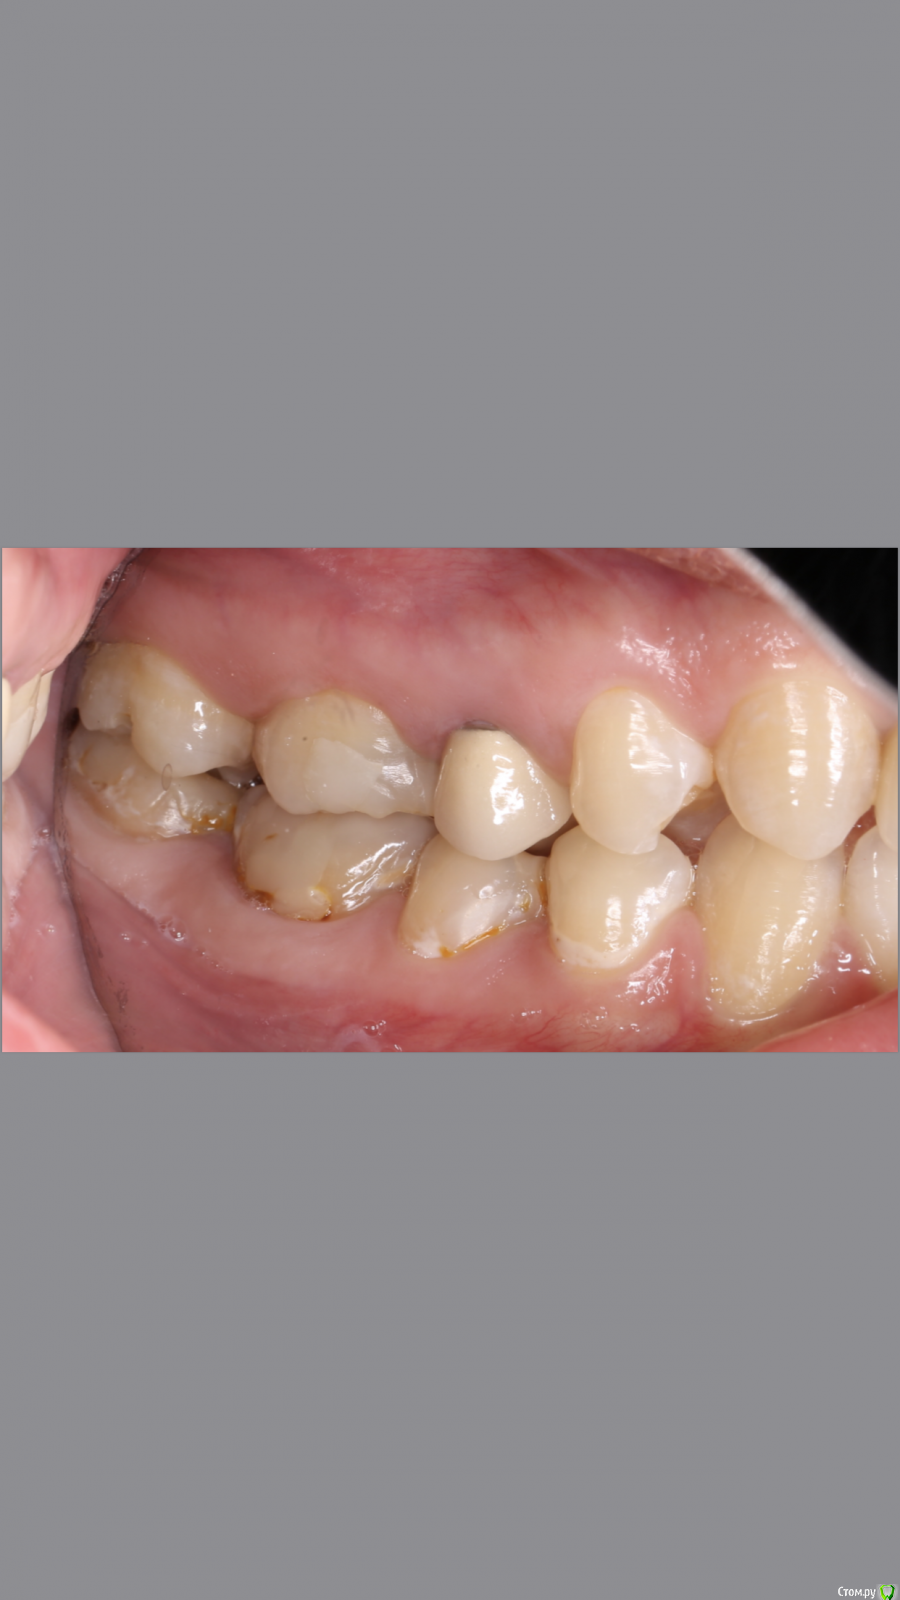

dr.Dre Опубликовано 8 июня, 2019 Поделиться Опубликовано 8 июня, 2019 Добрый вечер.Коллеги помогите грамотно скласть план лечения?С чего начинать ,терапия,ортодонтия ортопедия Ссылка на комментарий

Monkey Опубликовано 19 июня, 2019 Поделиться Опубликовано 19 июня, 2019 Добрый вечер.Коллеги помогите грамотно скласть план лечения?С чего начинать ,терапия,ортодонтия ортопедияСанация, удаление 8-х, ортодонтическое лечение с раскрытием места 36,23 (заодно и среднюю линию откорректируете), протезирование Ссылка на комментарий